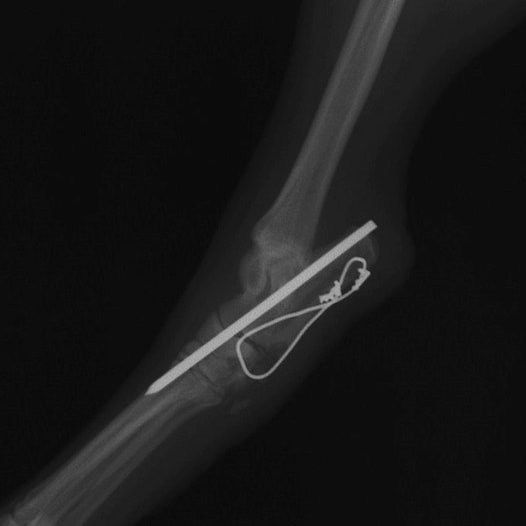

症例:柴犬 3歳

左後肢の完全挙上を主訴に来院されました。触診にて近位足根関節の過伸展を、レントゲン検査にて左足根関節周囲の軟部組織の腫脹、ストレス撮影によって距骨・踵骨と第4足根骨・中心足根骨間の脱臼および過伸展を認めました。

術中において、浅趾屈筋腱を剥離、内方へ牽引し、直接踵骨から第4足根骨までピンを挿入し(あらかじめ細いピンで下穴をあけておくとよい)、テンションバンドワイヤー法を併用し、関節軟骨の掻爬と海綿骨移植を実施しました。

術後レントゲン画像上に癒合が認められるまで約2ヵ月間は、運動を制限する必要があります。

術前正面像左関節の腫れ

左足根関節の軟部組織が腫脹しています。